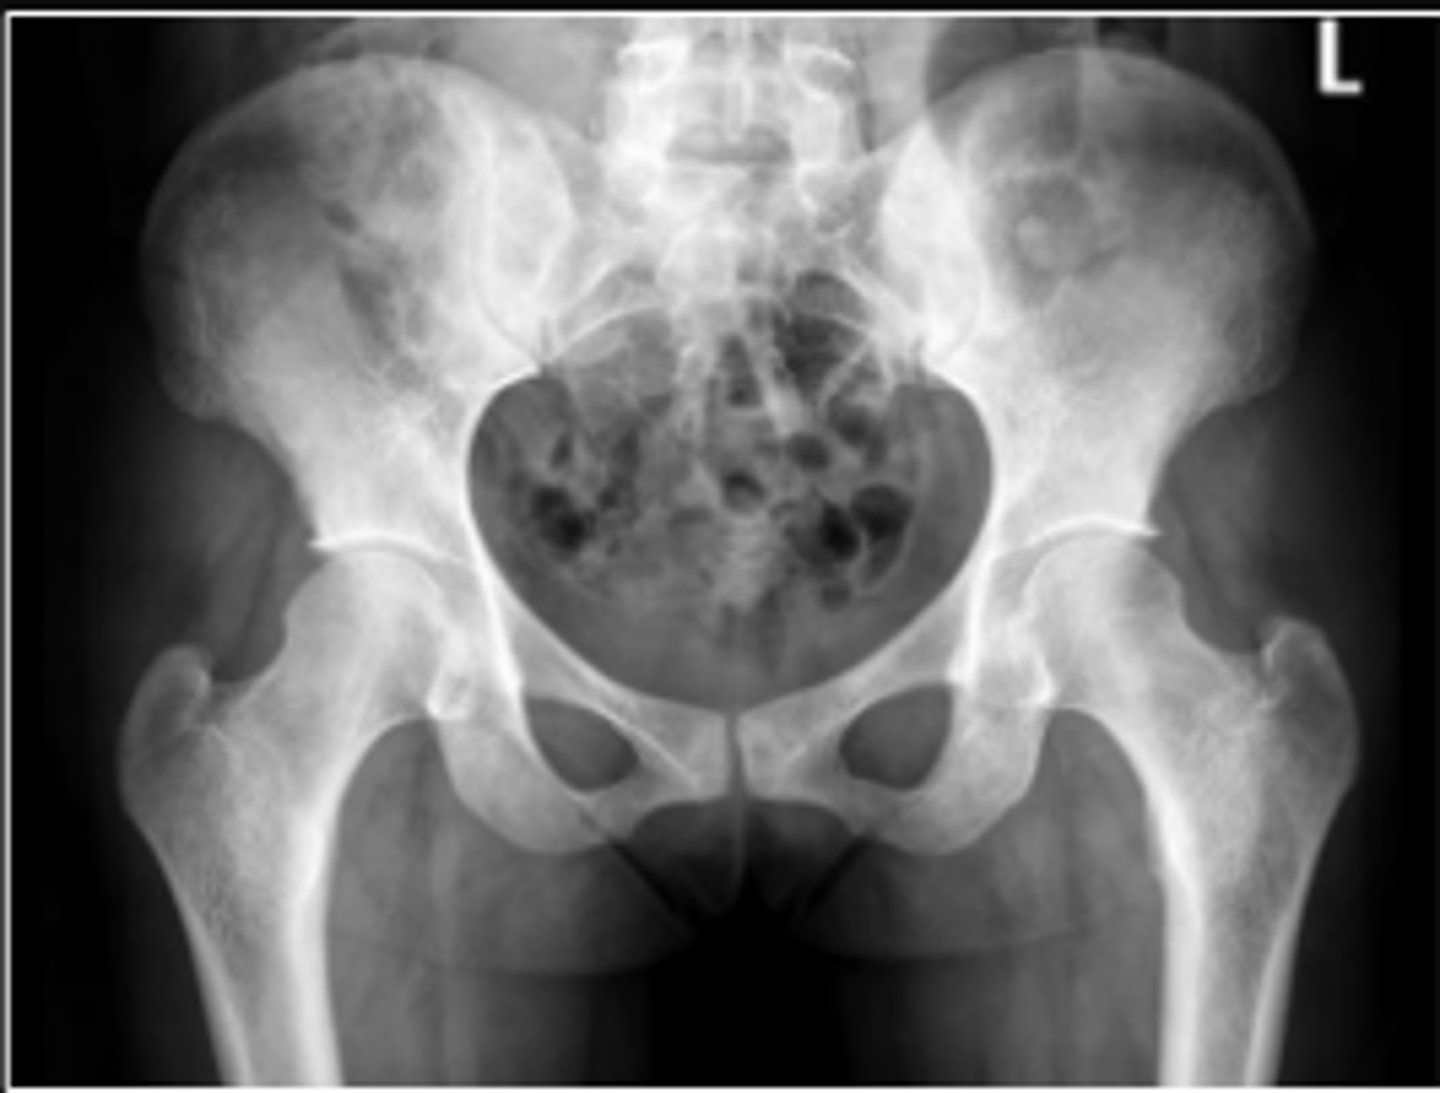

AP pelvis or bilateral hips

What is the name of the radiographic view?

Right iliopectineal line

What is the name of the assessment?

Right ilioischial line

Center edge angle

20-40 degrees

What is the normal range for this assessment?

A vertical line is drawn upwards from the center

of the head of the femur.

The second line is drawn from the center of the femur head to the outer superior-lateral aspect of the acetabulum

What are the osseous landmarks for this assessment

No (normal measurement is 20-40 degrees)

Is the measurement within normal limits?

Acetabular dysplasia

Developmental dysplasia of the hip

Name 1 condition that may result in a measurement <20 degrees?

AP pelvis and AP hip views

Name 2 radiographic views for this assessment?

A mechanical instability of the femoroacetabular

joint characterized by a shallow acetabulum

providing insufficient covering of the femoral

head

What is developmental hip dysplasia?

AP right hip

What is the radiographic view?

Teardrop distance

6-11mm

The distance between the most medial margin of

the femoral head and the adjacent pelvic

teardrop

What are the osseous landmarks for this assessment?

Yes (normal is 6-11mm)

Femoroacetabular joint inflammation

Name 1 condition that may result in a measurement of 15mm?

Late stage degenerative joint disease

Protrusio acetabuli

Name 2 conditions that may result in a measurement of 3mm?

Waldenstrom's sign

What is the named sign if this assessment has a value > 2mm difference

between the left and right side?

Hip joint space width

Superior joint space is 3-6mm

Axial joint space is 3-7mm

Medial joint space is 4-13mm

Superior joint space-> The measurement between the most convex superior aspect of the femoral head and the adjacent acetabulum

Axial joint space -> The measurement between the

femoral head and the acetabulum lateral to the

acetabular notch

Medial Joint space -> The measurement between the most medial margin of the femoral head and the adjacent pelvic teardrop

Yes

Are the measurements within normal limits?

Degenerative joint disease

Name 1 condition that may result in a measurement of <3mm for the superior joint space?